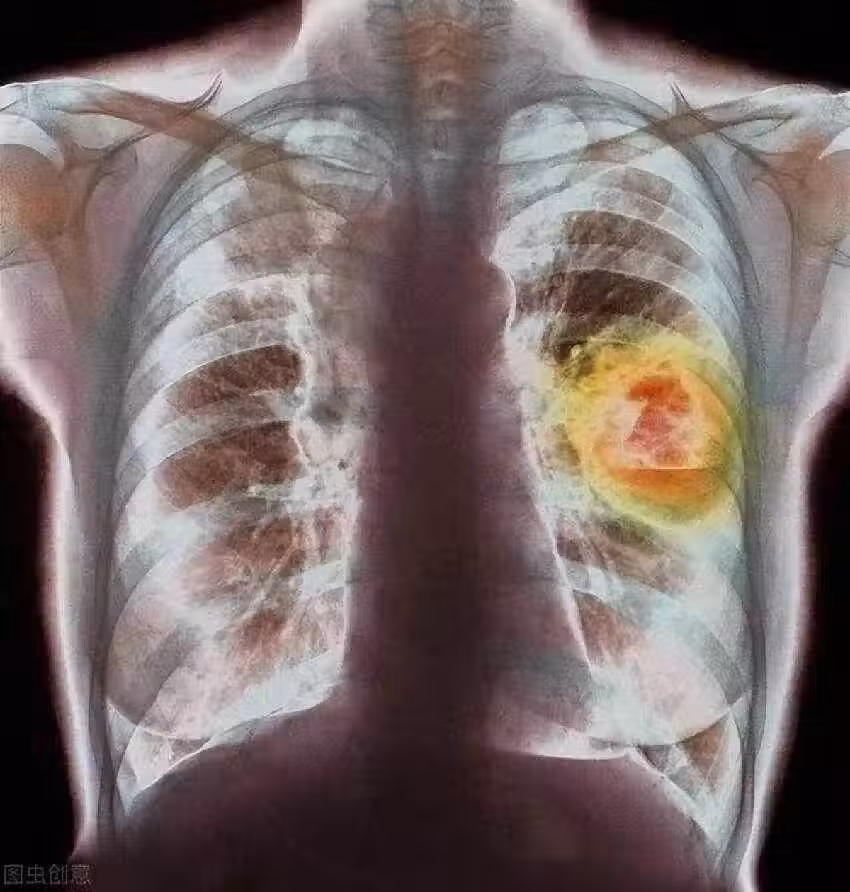

58歲婦女確診肺癌,強忍淚水坦言:手部早出現了問題,沒有多重視

當李阿姨第一次見到醫生時,她仔仔細細地把自己的症狀說了個遍,還提到這段時間為了搞清楚身體狀況,她沒少研究各類健康知識。

在詳細詢問了李阿姨的生活和飲食習慣後,醫生突然拋出一個看似和腹瀉八竿子打不著的問題:「您的手有沒有什麼不一樣的感覺? 比如說麻木、疼,或者使不上勁?」

李阿姨一下子愣住了,腦海里像閃電划過一般,突然想起來自己的手確實有點不對勁。

可之前她一直覺得,自己年紀大了,平時又總整理書籍,有點手部勞損很正常,壓根沒往別的地方想。